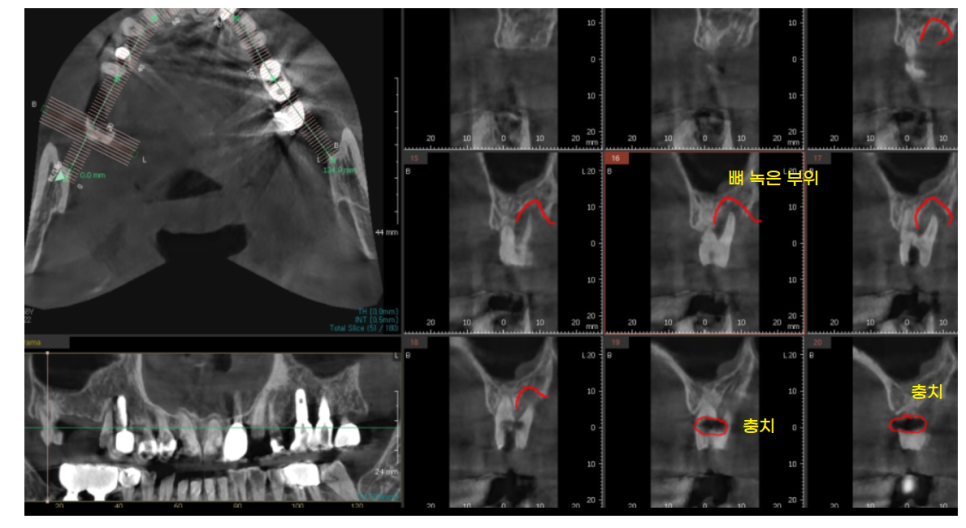

환자분께 설명 드렸던 사진입니다.

동그라미로 표시한 부위가 충치입니다.

단순히 충치만 있는 것이 아니라

한쪽 뿌리 뼈도 많이 녹아

검정색으로 보이네요~

해당 치아는 치료를 하더라도 몇개월 안가

문제가 생길듯 하였습니다

기회비용을 생각하여

당일 문제 치아 발치 후 상악동 거상술을 동반한 뼈이식

진행하였는데요.